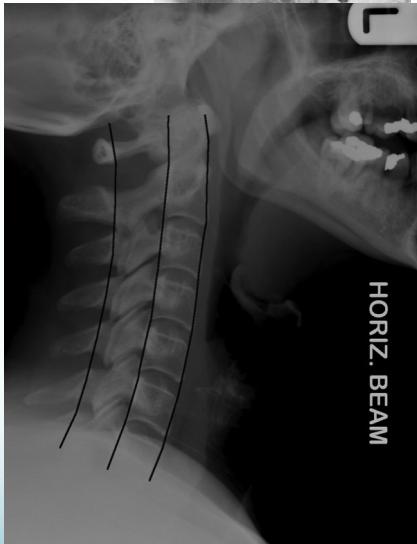

Lateral View

- All C- vertebrae & upper T1

- Prevertebral soft tissue width

- Four parallel curves

- Front of vertebral bodies

- Back of vertebral bodies

- Posterior borders of lateral masses

- Bases of spinous processes